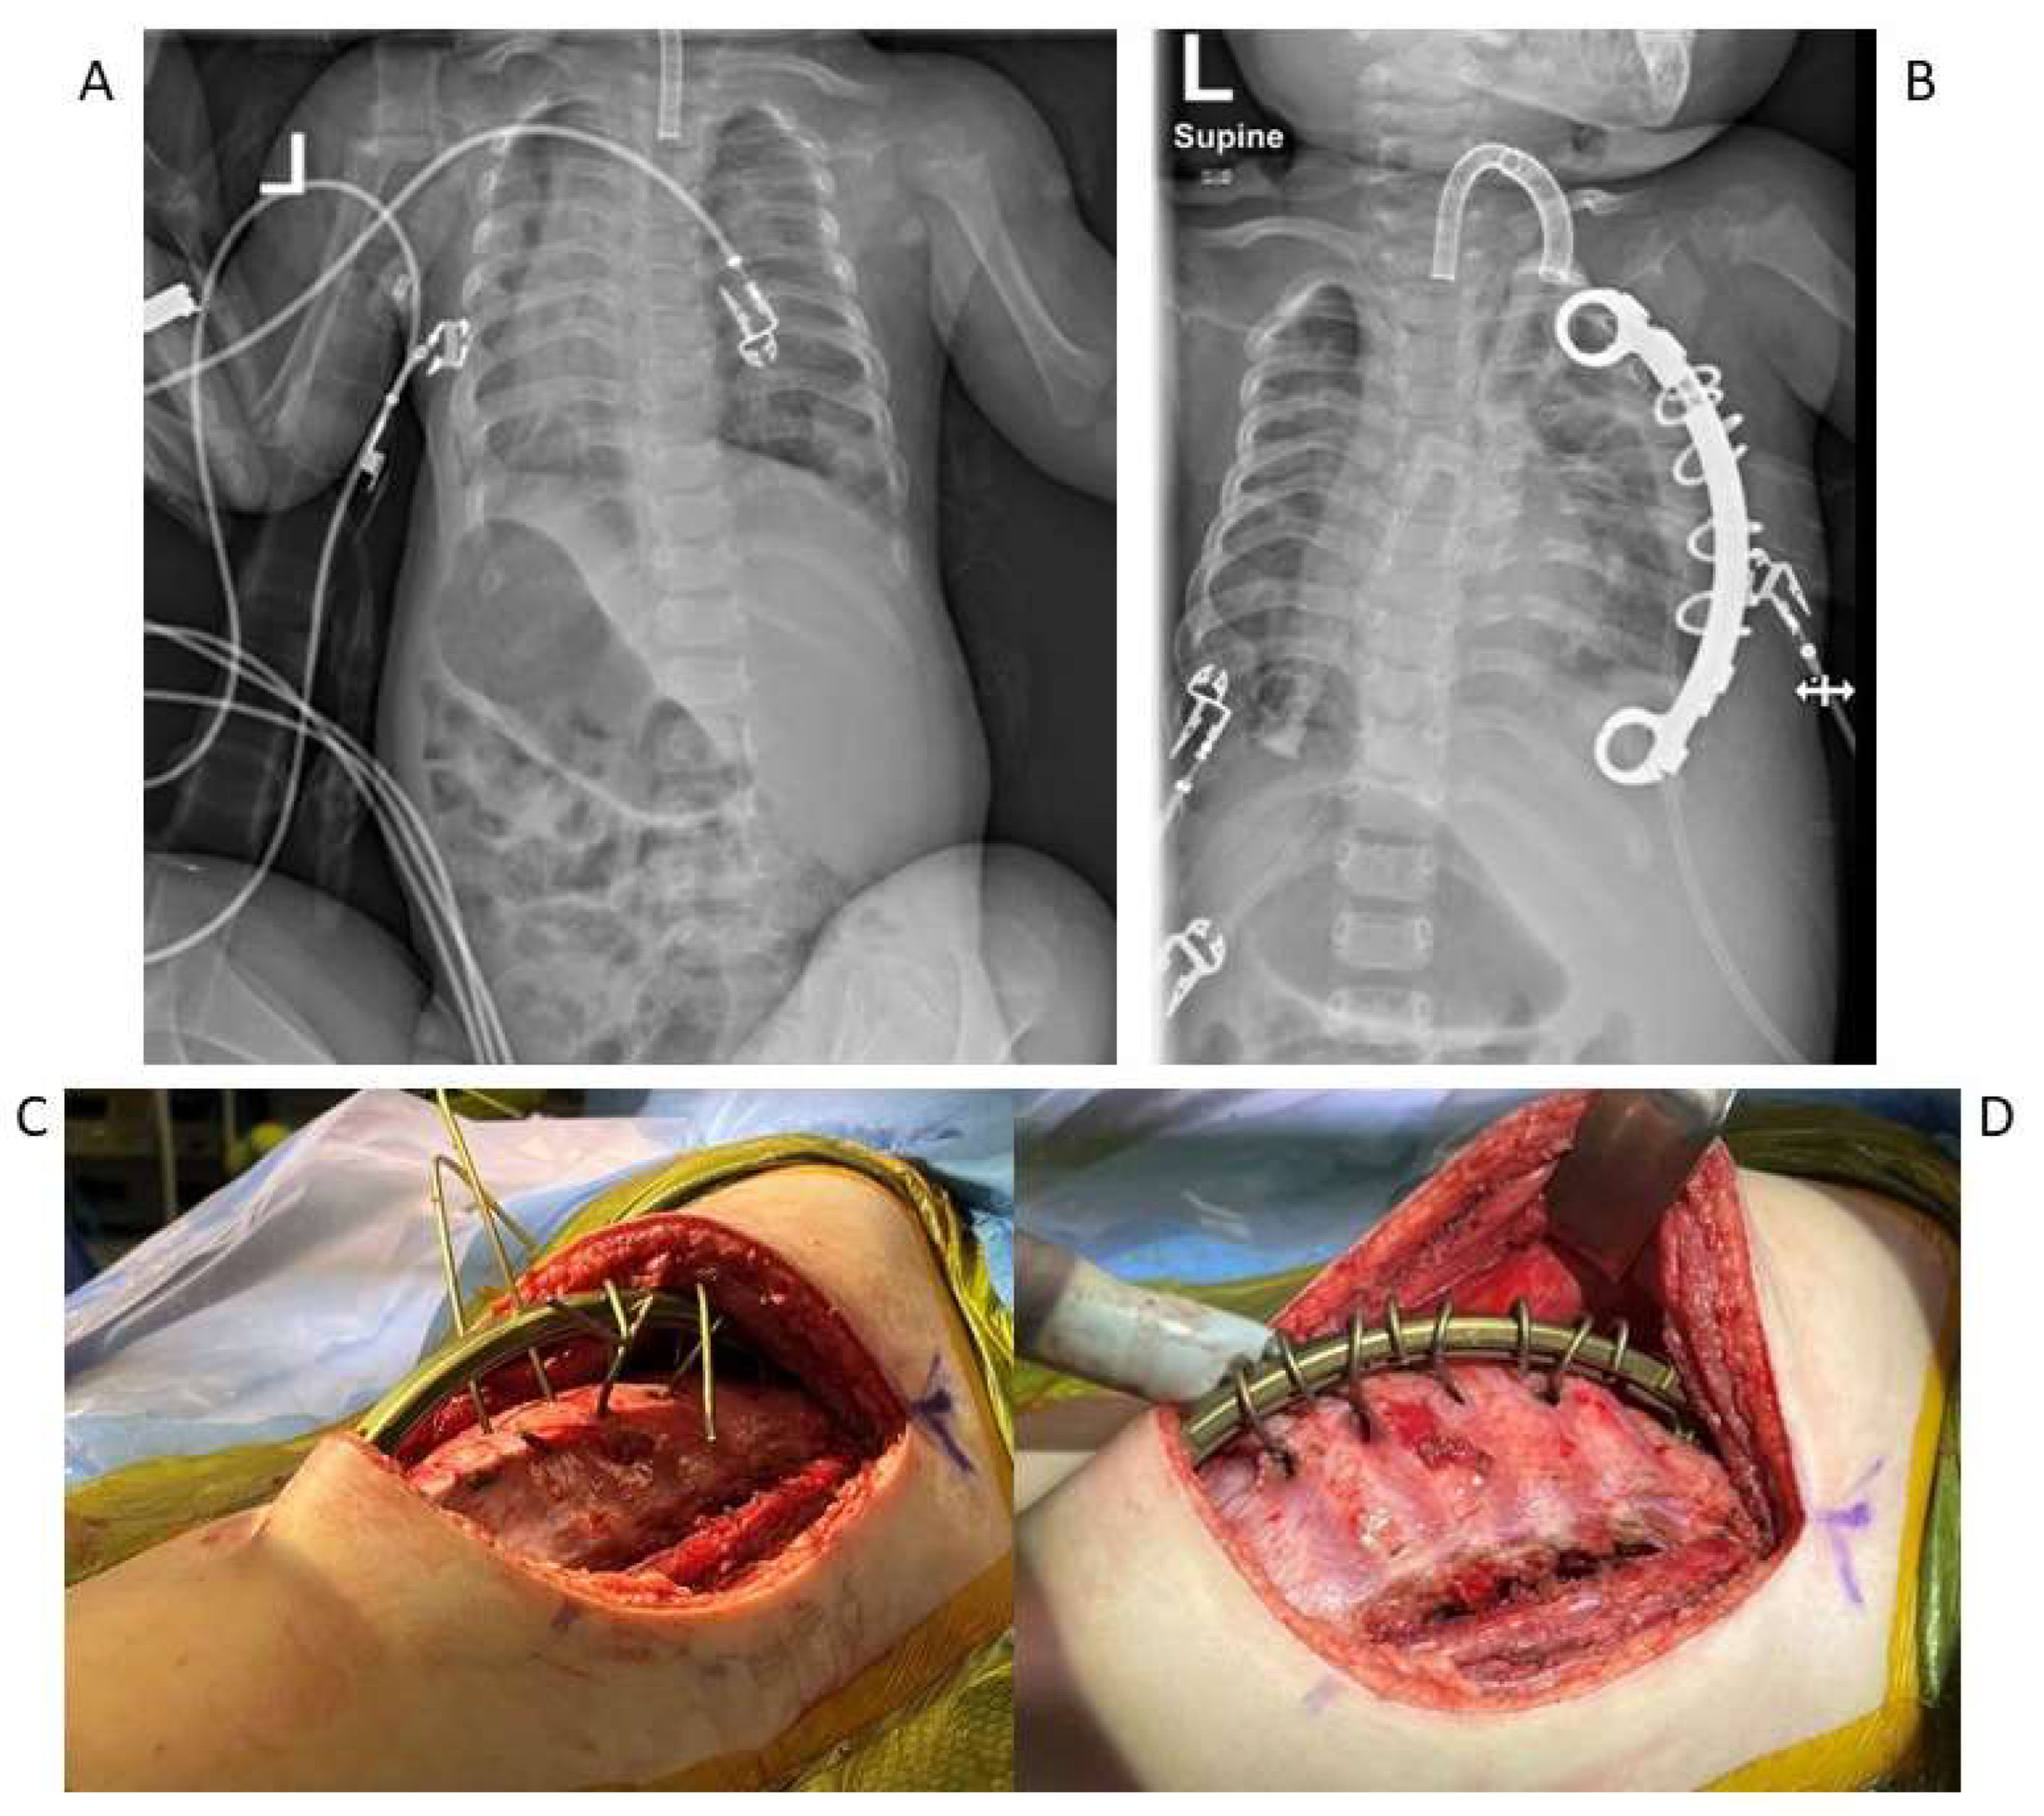

5. Surgical Management

- Campbell, R.M.; Smith, M.D.; Mayes, T.C.; Mangos, J.A.; Willey-Courand, D.B.; Kose, N. The effect of opening wedge thoracostomy on thoracic insufficiency syndrome. J. Bone Joint. Surg. Am. 2004, 86, 1659–1674. [Google Scholar] [CrossRef]

- Campbell, R.M.; Vocke, A.K. Growth of the thoracic spine in congenital scoliosis after expansion thoracoplasty. J. Bone Joint Surg. Am. 2003, 85, 409–420. [Google Scholar] [CrossRef] [PubMed]

- Emans, J.B.; Caubet, J.F.; Ordonez, C.L.; Lee, E.Y.; Ciarlo, M. The treatment of spine and chest wall deformities with fused ribs by expansion thoracostomy and insertion of vertical expandable prosthetic titanium rib: Growth of thoracic spine and improvement of lung volumes. Spine 2005, 30, S58–S68. [Google Scholar] [CrossRef]